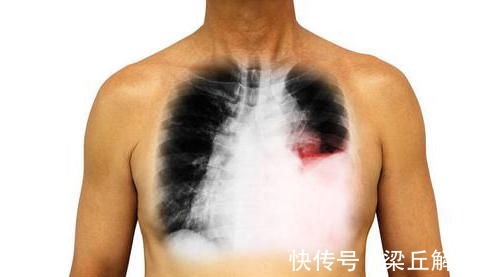

肺部疾病症状很多,大部分局限在肺,比如咳嗽、咳痰,气喘、胸闷,唯独肺癌与其他肺病不同,即使没有发生转移,也可能在肺以外部位出现症状,甚至发生在咳嗽、咳痰这些症状之前,如果能尽早想到肺部并及时诊治,可能延长生命,提高生活质量,减轻痛苦,如果肺癌还在早期,甚至可以手术根治。下面我们来看看都有哪些这样的表现。

单侧上肢或者胸部潮红出汗这种现象很多人会有,但大部分表现为左右交替出现,侧卧时靠上的一边容易出汗,但某些肺癌患者则表现为固定的一边出汗,上肢、胸部单独或者同时出现出汗及潮红现象,严重时会蔓延到面部,甚至会引起一侧眼皮下垂,瞳孔缩小,两只眼睛不一样大,这种肺癌大部分发生于肺尖部位,在肺的最上面,拍胸片容易遗漏,必要时做个CT,一目了然。